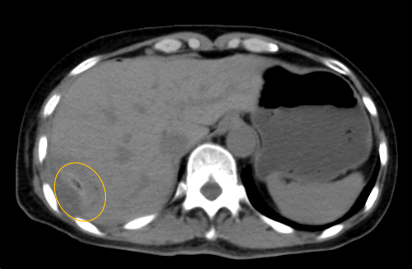

入院后,影像診療中心立即給李女士完善了CT和MR檢查,發(fā)現(xiàn)病變位于肝包膜下,臨近膈肌,消融治療過程中有并發(fā)損傷膈肌的可能,難度較大,但是采用精準(zhǔn)影像定位是可以完成的。陳寶瑩主任立即與腫瘤三病區(qū)劉金鵬主任聯(lián)系,并與影像微創(chuàng)治療小組進(jìn)行MDT討論:患者為卵巢癌肝右葉包膜下單發(fā)轉(zhuǎn)移瘤,最長徑不超過3cm,患者對局部治療的主觀愿望強(qiáng)烈,符合消融治療專家共識,遂制定了影像引導(dǎo)下局部消融治療聯(lián)合全身治療的綜合治療方案。

針對這個特殊部位的腫瘤,要想消融完全,那么膈肌損傷的風(fēng)險(xiǎn)就很高,陳寶瑩主任帶領(lǐng)影像微創(chuàng)亞專業(yè)組成員仔細(xì)閱讀CT圖像,設(shè)計(jì)進(jìn)針路徑,結(jié)合MR圖像確定腫瘤活性范圍,制定了周密而詳盡的消融計(jì)劃。臘月二十九,即住院第二天影像微創(chuàng)治療小組圓滿為患者完成了腫瘤微波消融治療,觀察24小時后出院回家過年。術(shù)后48小時隨訪患者無明顯不適,術(shù)后7天隨訪,患者肝功、血常規(guī)等各項(xiàng)指標(biāo)均恢復(fù)正常。